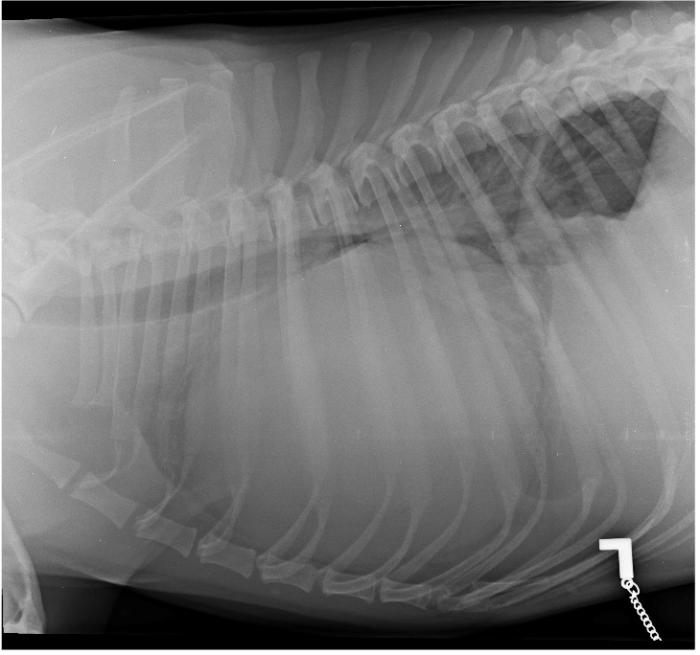

Se obtienen imágenes radiológicas del tórax en proyección laterolateral izquierda y derecha tras sedación ligera con butorfanol/midazolam vía endovenosa. En ambas proyecciones se observa una importante cardiomegalia generalizada, con un índice cardiaco vertebral igual a 16 (10.22 ± 0.20). Además, se aprecia una marcada elevación traqueal y compresión de la carina traqueal acompañado de elevación traqueal (Figura 1A-B). Estos hallazgos son compatibles con cardiomegalia o presencia de derrame pericárdico.

Figura 1. Radiografías de tórax del paciente en su proyección (A) laterolateral izquierda y (B) derecha, en las que se aprecia evidencia cardiomegalia.